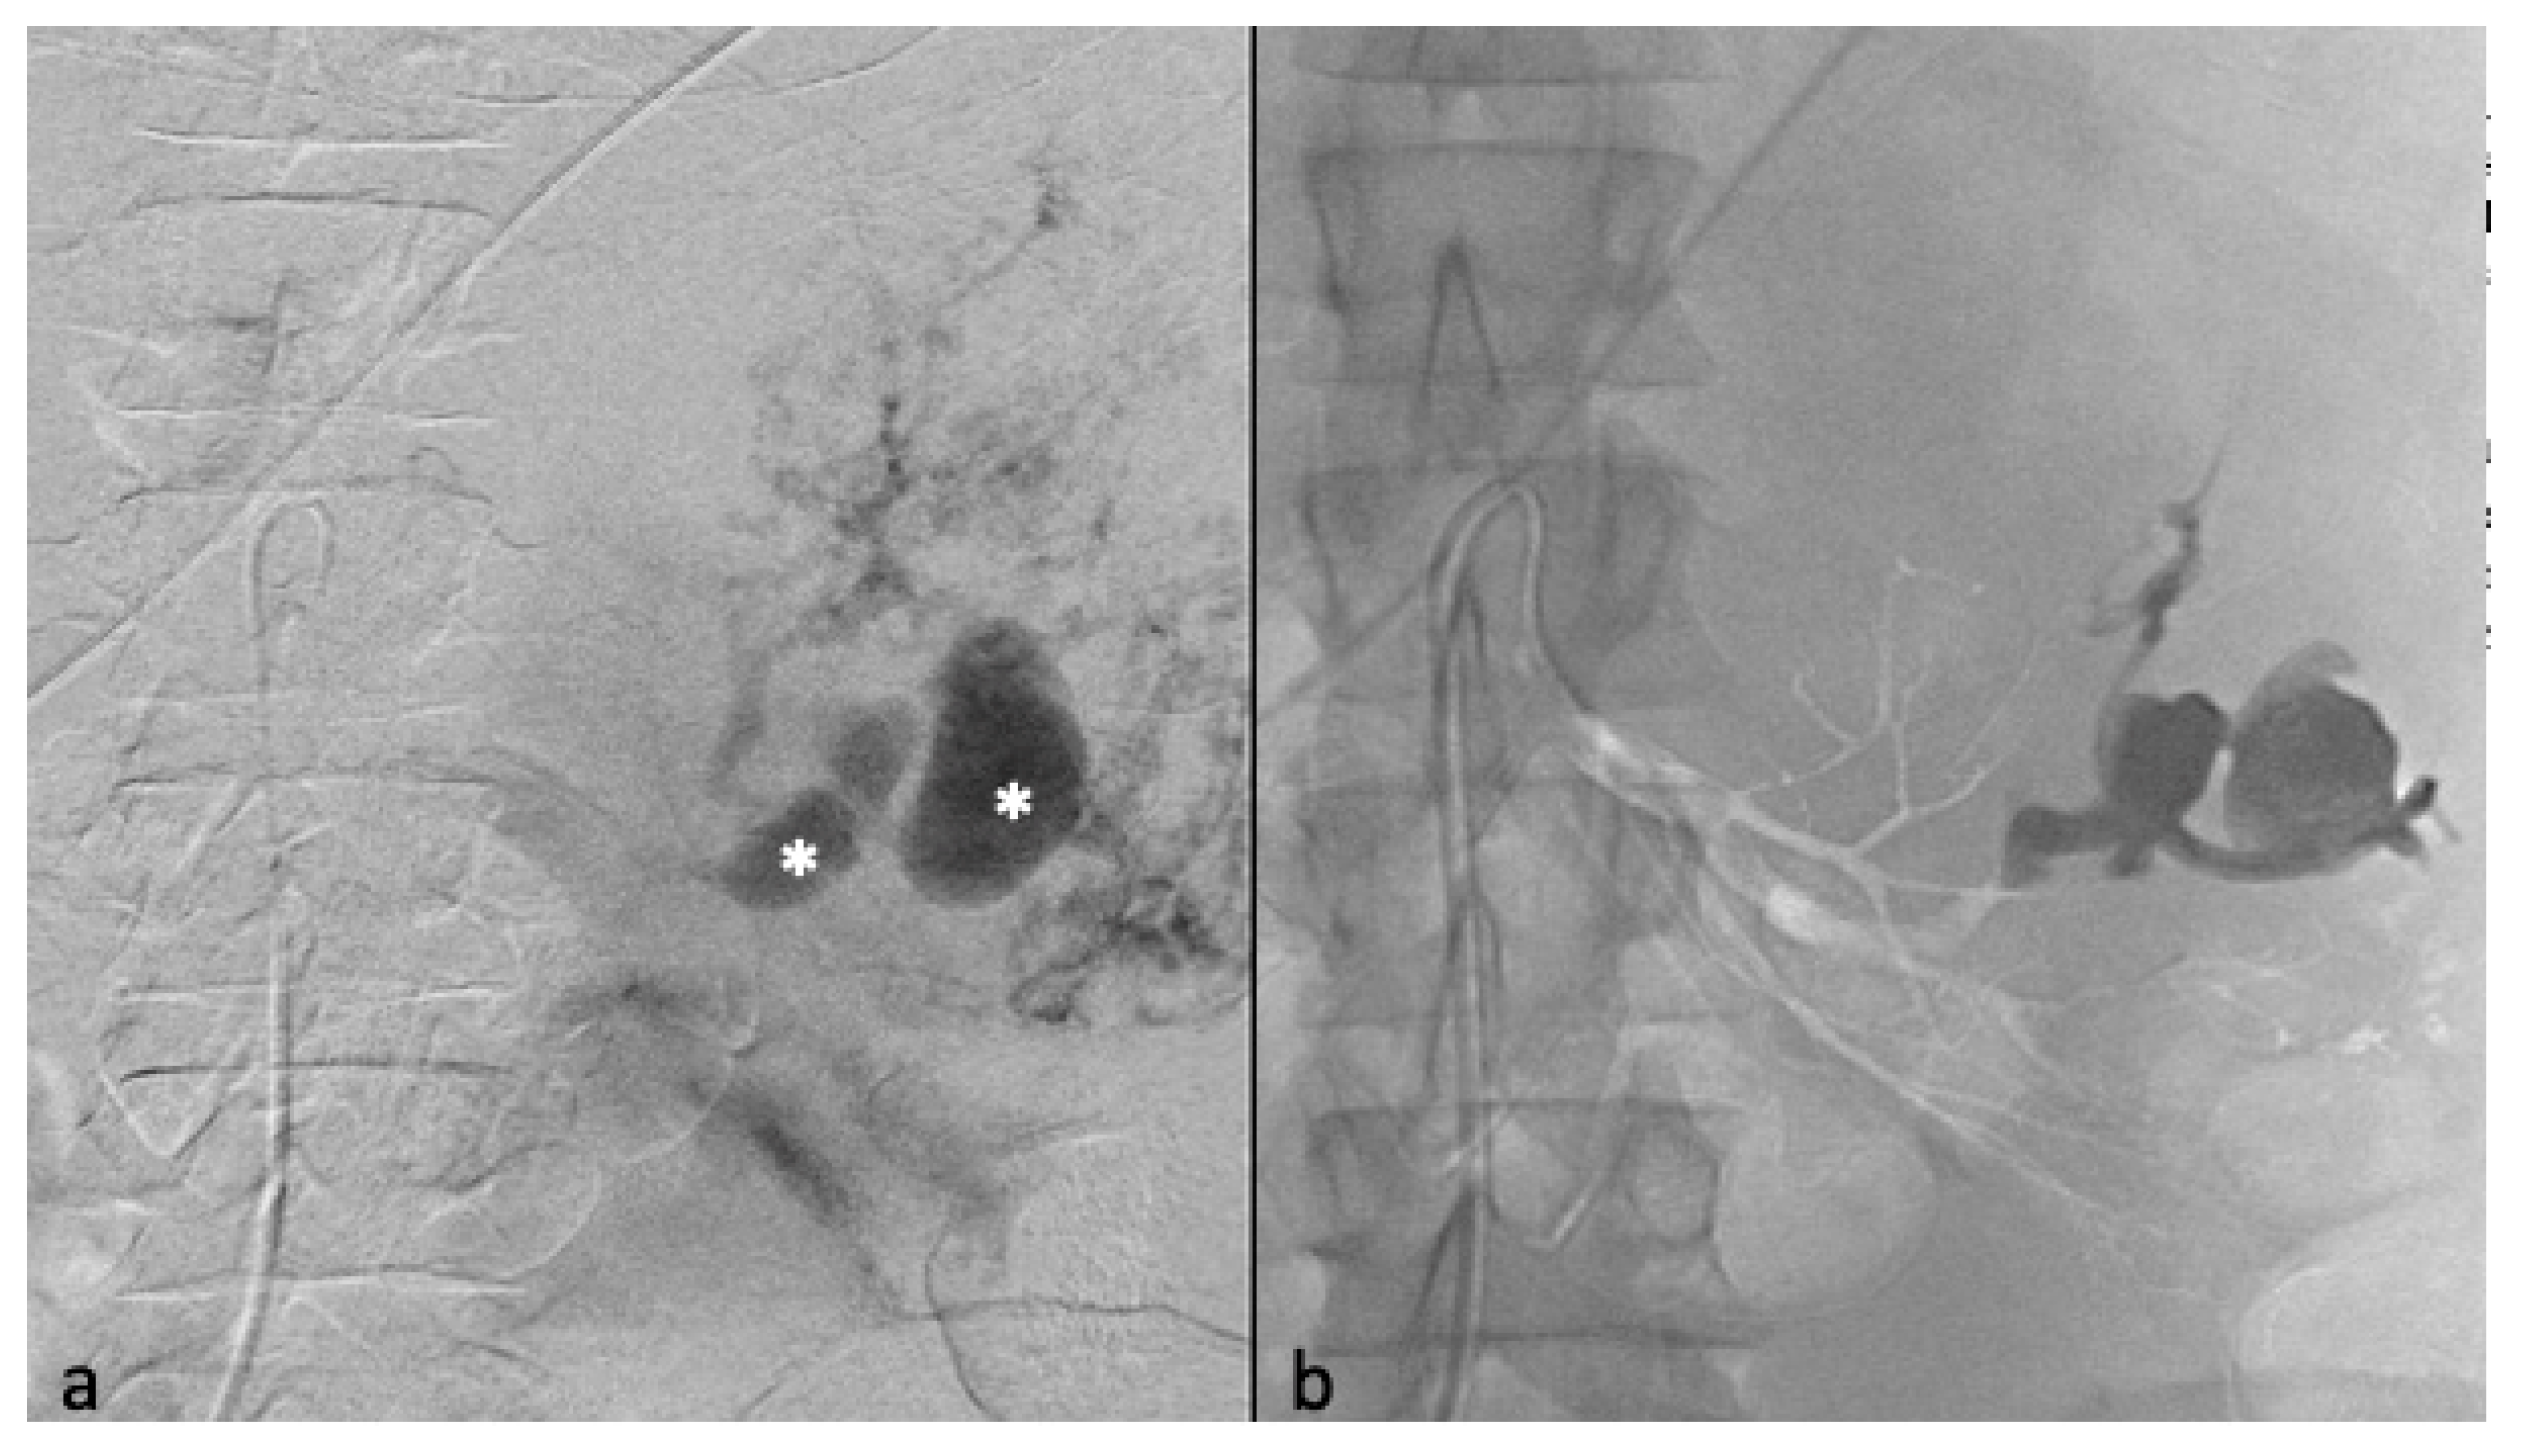

Figure 2.

Selective arterial embolization (TAE) of a large right AML. (a) Angiography shows two feeding arteries to the AML with multiples aneurysms. (b) The hypervascularity and dysplastic vessels of this AML are typical. (c) Final control after TAE of two arterial branches with ONYX 18 (6% EVOH) with technical success (lack of opacification of the AML).

Postembolization angiography performed through the 6-F catheter confirmed successful occlusion of the artery and the patency of other renal arteries branches. Technical success was defined as no opacification of the main feeding arteries and lack of AML staining on the post-TAE angiography after one embolization (primary technical success) or two (secondary technical success) (Figure 3).

Figure 3.

Transarterial embolization (TAE) of an AML with massive aneurysms. (a) Angiography shows one AML on the upper pole of the left kidney with massive aneurysms (*) (b) Final control after TAE of the main arterial branch with ONYX 18 (6% EVOH) and technical success (lack of opacification of the AML).